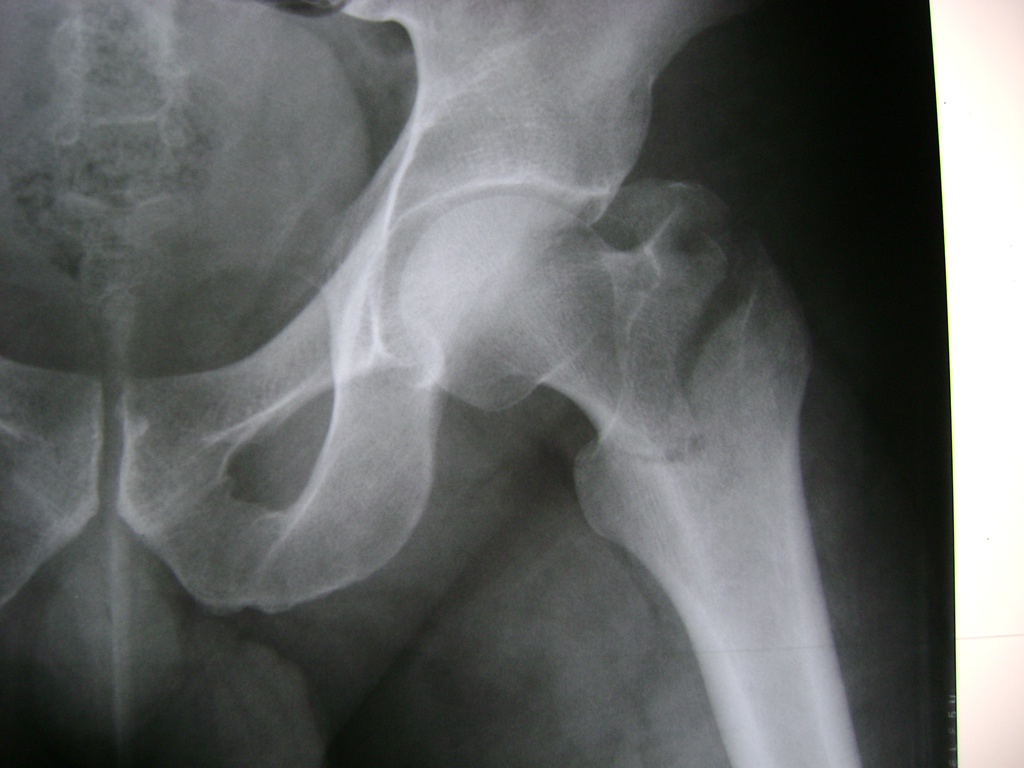

Cirugía de Fémur - Cadera

La cirugía de fractura de cadera se realiza para reparar una ruptura en la parte superior del hueso del muslo. Este hueso se denomina fémur.

Es parte de la articulación coxofemoral. Si una fractura de cadera no recibe tratamiento, es posible que deba permanecer en una silla o en la cama.